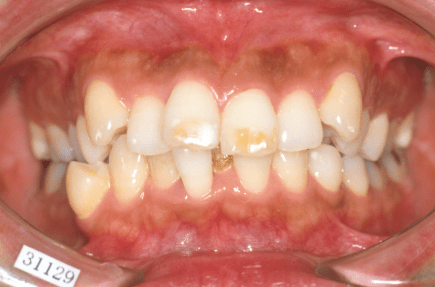

叢生とは、歯並びがデコボコの状態のことを指します。

叢生(デコボコ)

原因:歯の大きさと顎の骨の横幅のアンバランス

この他にも、子供の歯並びから永久歯への生え変わりがうまくいかなかったり、虫歯などで子供の歯を早くに失ってしまったことで、叢生が生じてしまう方もいらっしゃいます。歯並び・かみ合わせは人生を通して常に変化するものですから、食いしばりの癖が強い方などは年齢を重ねるにつれ叢生がひどくなってきたとおっしゃられる方もおられます。